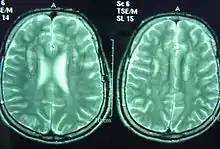

Sjögren–Larsson syndrome is a rare autosomal recessive form of ichthyosis with neurological symptoms.[1]: 485 [2]: 564 [3] It can be identified by a triad of medical disorders. The first is ichthyosis, which is a buildup of skin to form a scale-like covering that causes dry skin and other problems. The second identifier is paraplegia which is characterized by leg spasms. The final identifier is intellectual delay.

Without a functioning fatty aldehyde dehydrogenase enzyme, the body is unable to break down medium- and long-chain fatty aldehydes which then build up in the membranes of the skin and brain.[4]